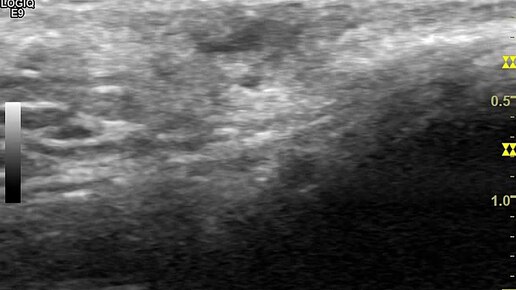

Видео к статье: "Вросший волос. Псевдофолликулит"https://dzen.ru/a/aAX774WVVxqVhJ-B

Ультразвуковые находки от врача УЗД Зорина Я.П.